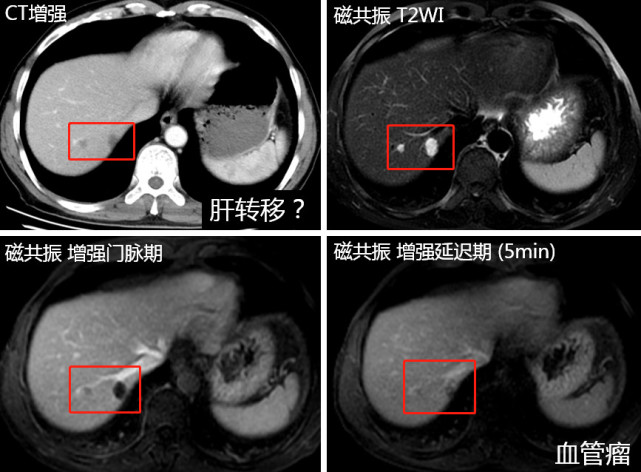

图片(患者的CT与磁共振结果,红框内为可疑结节)

这位肠癌患者在做术前CT分期时,在肝脏上看到了两枚模糊的结节,这个时候是要考虑肝转移的,但是因为CT的软组织分辨率有限,对于一些不典型转移和良性病灶鉴别起来比较困难。而该病例如果确定肝转移,治疗选择就会不一样,可能会从直接手术转为先化疗再手术。

所以我们在MDT(多学科诊疗)讨论后建议先进行MRI(磁共振)检查进一步确认。MRI软组织分辨率优于CT,对肝转移鉴别的准确率更高。后来这位患者做了MRI后发现,肝脏结节是一个典型肝血管瘤的表现,而肝血管瘤是良性肿瘤,这么小是不需要任何处理的。后来患者放心进行了肠癌手术,至今生存超过五年没有复发。